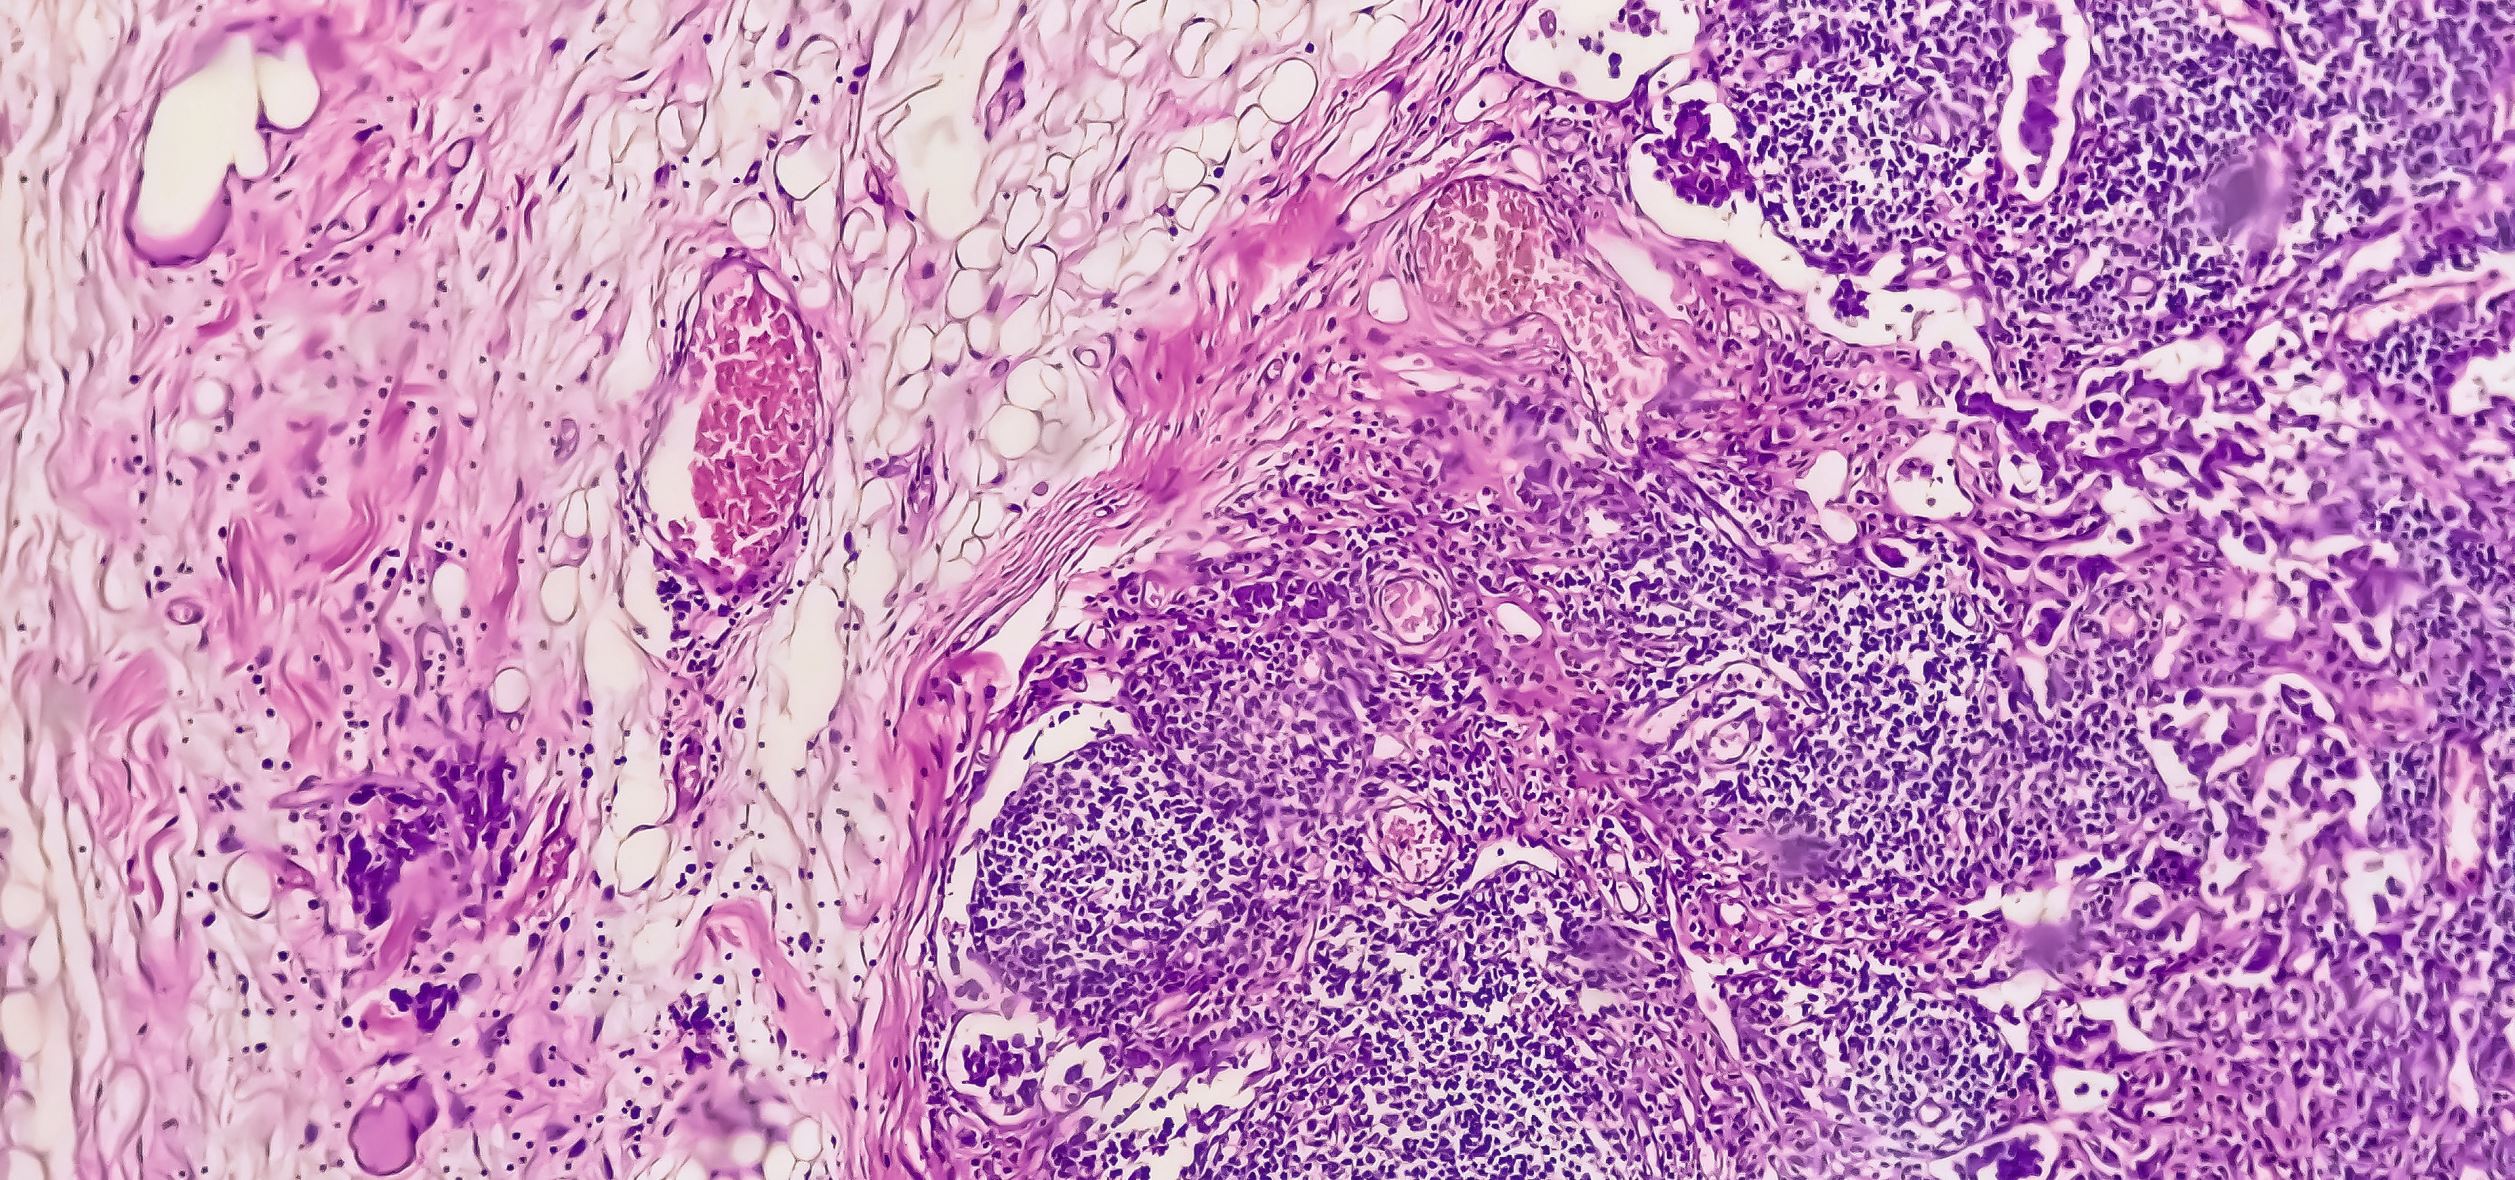

Oft bleiben Adenokarzinome des Magens und des ösophagogastralen Übergangs lange unentdeckt. Konzepte aus der kürzlich veröffentlichten S3-Leitlinie können die Prognose allerdings entscheidend verbessern.

© Saiful52 / stock.adobe.com